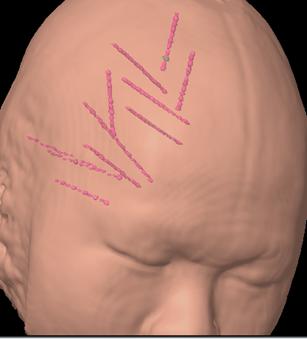

经科室病例讨论,外六科吴杰主任考虑患者癫痫灶位于右侧额颞部可能性大。为精确定位癫痫灶,几日后,医生全麻下行“右侧额颞顶深部电极置入术”。共植入11根脑深部电极。

术后监测记录立体脑电图(SEEG),记录到多次发作事件,明确了癫痫灶起源位置及癫痫放电的传播路径。

根据脑电图记录的结果,患者癫痫为右颞起源,向右额传导。半月后在局麻下行“右额颞癫痫灶颅内电极毁损术”。毁损右颞癫痫灶过程中患者有短暂而轻微的局灶性癫痫发作一次。手术过程顺利,术中、术后小刘无不适感。术后无功能障碍。

术后复查MR图像,传入导航系统,与之前的计划融合,见毁损灶定位精确。患者恢复迅速而良好,至今无癫痫发作。